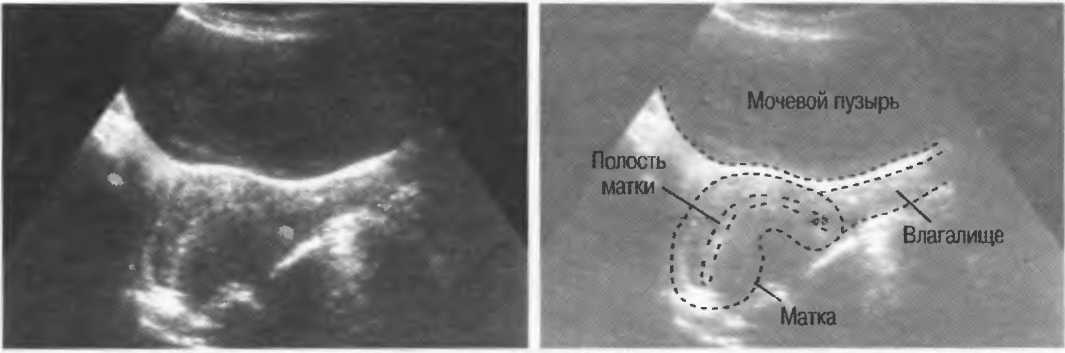

Рис.20в. При сканировании матки через наполненный мочевой пузырь параллельные датчику слои тканей передней брюшной стенки могут вызывать появление ревербераций, которые определяются как зхоструктуры в передних отделах мочевого пузыря на фоне анэхогенной полости. Поперечный срез (слева) отличается от продольного среза (справа) при изменении положения датчика.